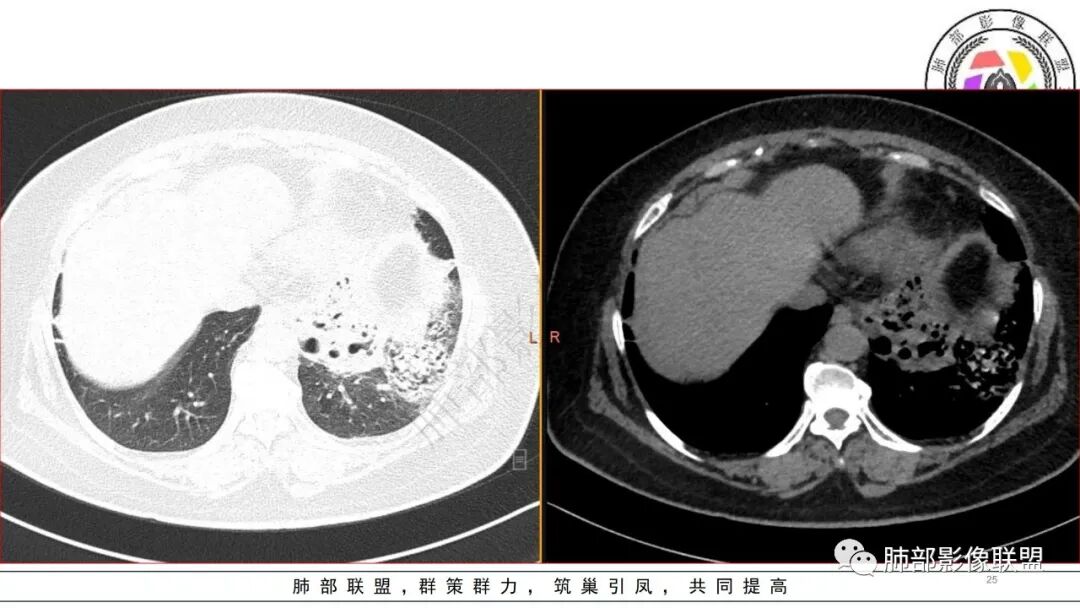

3.五天后及十三天后病灶变化明显,实性密度影吸收缩小,边界趋于清楚,显示多空腔。

糖尿病基础,左下肺感染性病变,进展快,先是左肺大片实变,短时间复查出现空洞,治疗两周周边有吸收好转,空洞壁变薄。金毛结克,我倾向金葡菌。鉴别肺克。

女,61,糖尿病史,CRP、血像、ESR、CA199等增高,白蛋白低。胸部CT:左下肺大片实变影,边缘模糊,短期复查部分吸收,多发空洞形成,成簇,大小不等,无液平。考虑,金葡?肺克?奴卡?鉴别支扩伴感染、CPAM等。